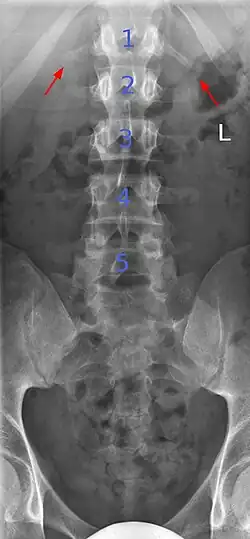

Lumbarization of sacral vertebra 1, seen as 6 vertebrae that do not connect to ribs.

Lumbarization is an anomaly in the spine. It is defined by the nonfusion of the first and second segments of the sacrum. The lumbar spine subsequently appears to have six vertebrae or segments, not five. This sixth lumbar vertebra is known as a transitional vertebra. Conversely the sacrum appears to have only four segments instead of its designated five segments. Lumbosacral transitional vertebrae consist of the process of the last lumbar vertebra fusing with the first sacral segment. [1] While only around 10 percent of adults have a spinal abnormality due to genetics, a sixth lumbar vertebra is one of the more common abnormalities. [2]